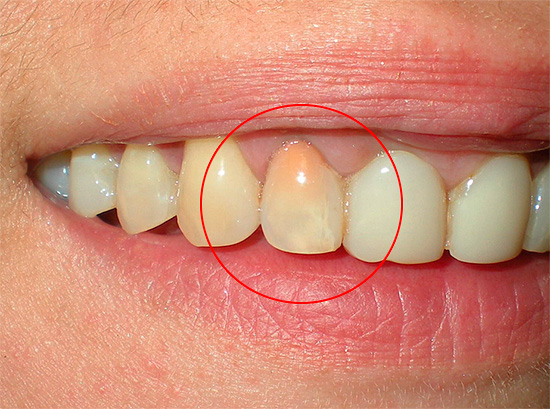

A foto abaixo mostra uma seção de um dente com uma cárie através da qual a infecção entrou na câmara pulpar: